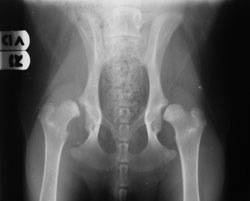

Next, x-rays of the pelvis are taken. Radiography is the only true means of reaching a definitive diagnosis of CHD. On x-ray, a healthy hip joint shows a snug fit of the femur head against the acetabulum, with the acetabulum appearing to cover about three-fourths of the femur head. In dysplastic dogs, the femur head appears to jut away from the acetabulum, and more space is visible between the two bones. Displacement of the head of the femur is considered the hallmark of CHD.

1 Photo Credit: Creative Commons License